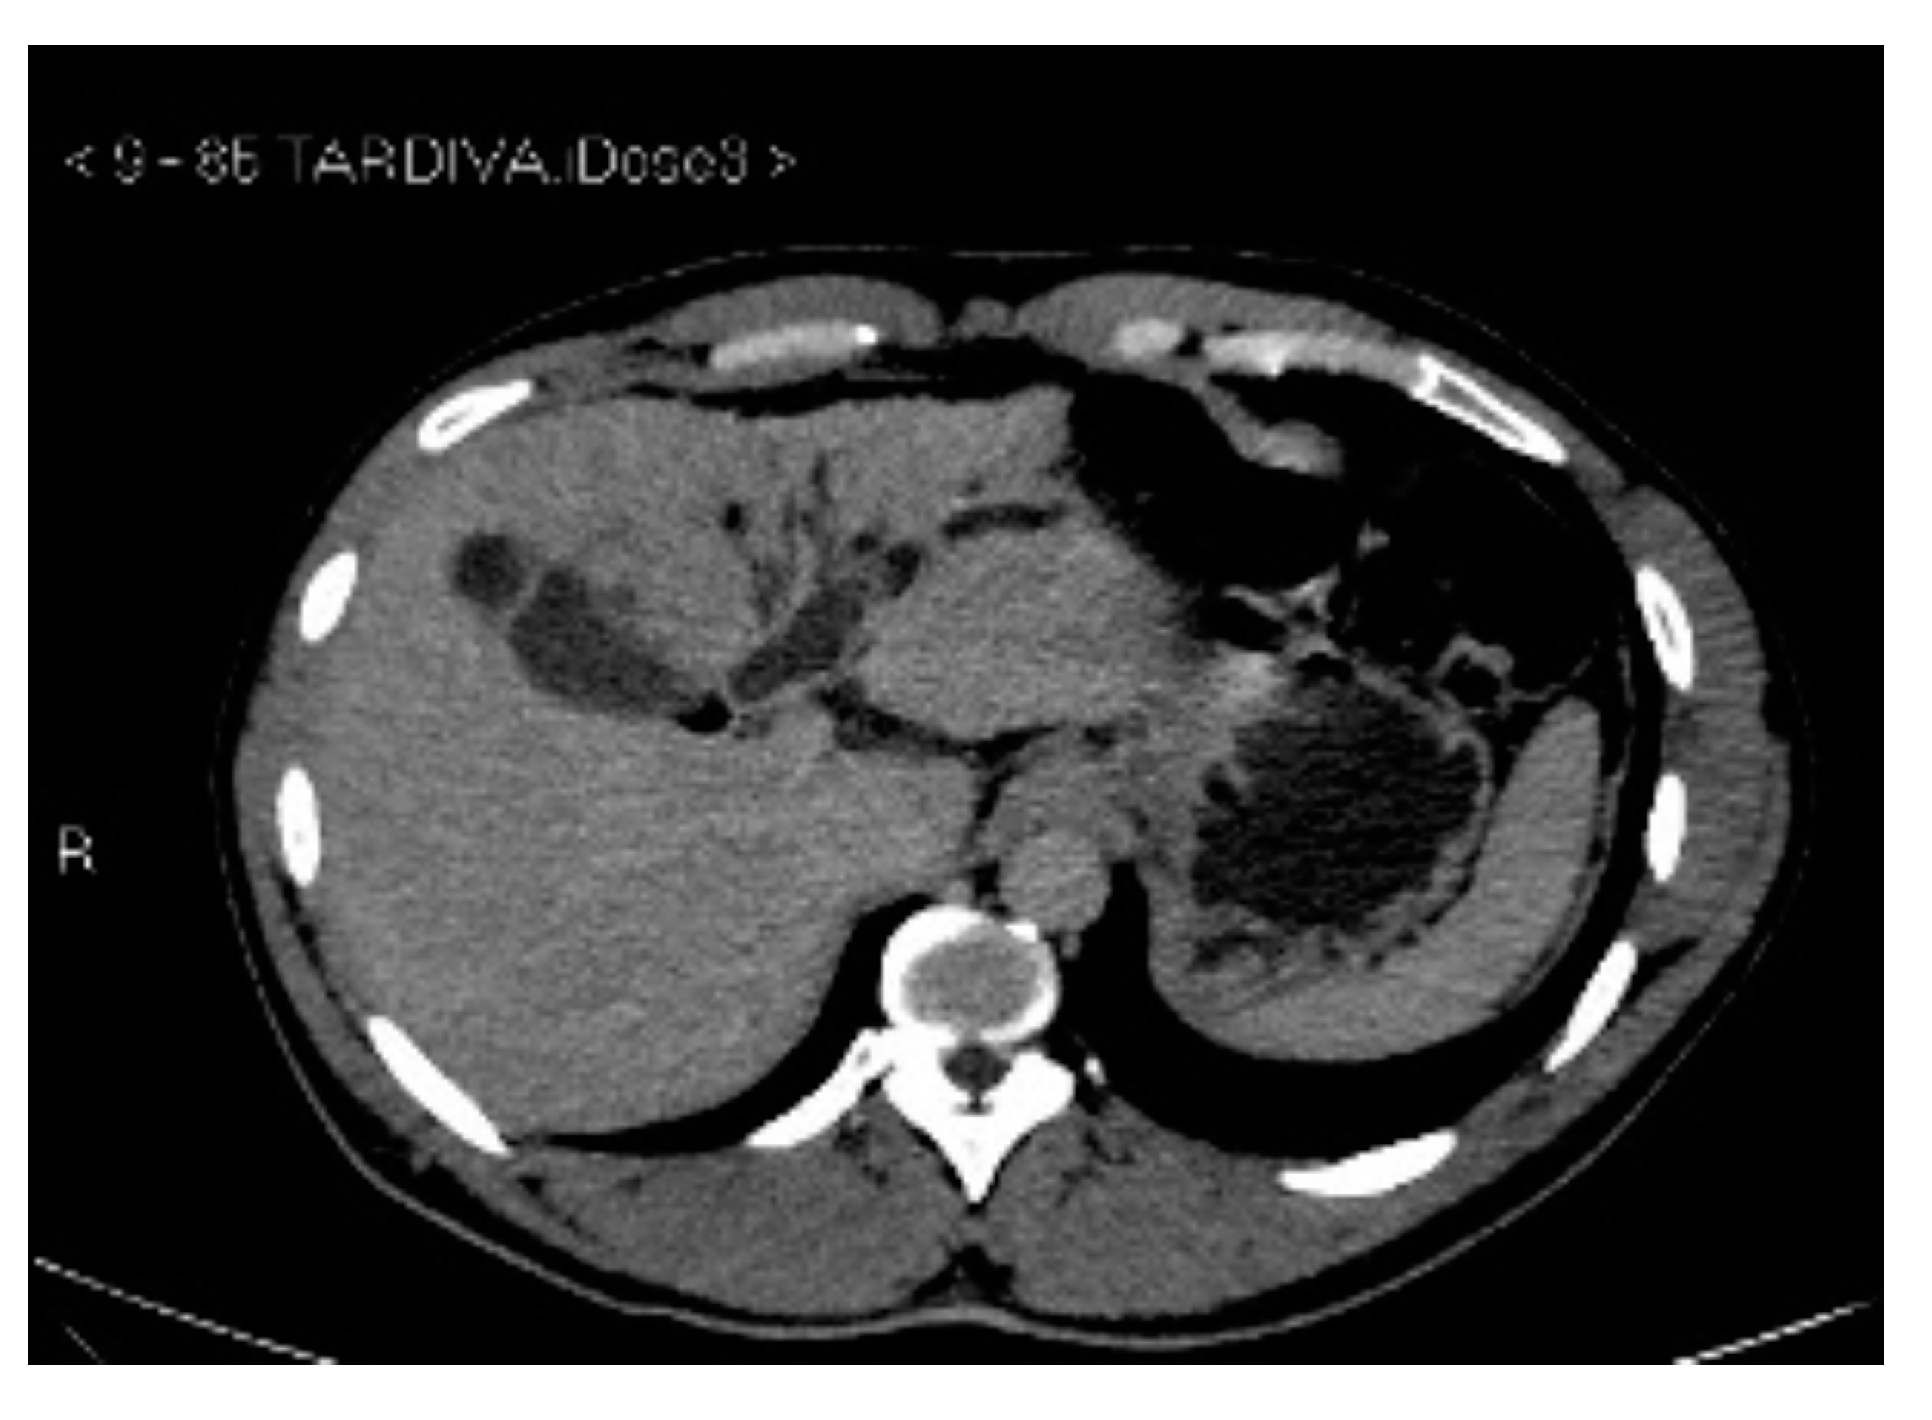

Subsequently, an upper-abdomen Computed Tomography (CT) scan and liver Magnetic Resonance Imaging (MRI) were performed (Figure 1, Figure 2, Figure 3, Figure 4, Figure 5, Figure 6 and Figure 7).

Figure 1.

CT arterial phase.

CT delayed phase.

A mass of 1.8 cm was detected within the biliary branch for the third hepatic segment, characterized by nodular impregnation in the arterial phase and irregular and partial washout in the portal venous phase. These findings were compatible with a heterologous lesion, although it was not possible to perform a diagnosis among HCC, intrahepatic CCA or other pathological lesions.

HCC typically has an increased arterial blood supply, so it usually shows hyperattenuation in the arterial phase and hypoattenuation in the portal venous phase, compared to the hepatic parenchyma.

Most HBDTTs should show the same enhancement pattern. However, some HCCs can show iso- or hypoattenuation in the arterial phase, with the enhancement in the arterial phase inversely correlated with the degree of blood clots and necrosis. So, hypoattenuation in the portal venous phase seems to be the most important imaging feature to distinguish HCC with BDTT from perihilar CCA [17].

In conclusion, the diagnosis of HCC with BDTT can be reasonably considered in the presence of lesions of both hepatic parenchyma and bile ducts with a cirrhotic underlined liver disease, especially if they show typical washout in the portal venous phase.